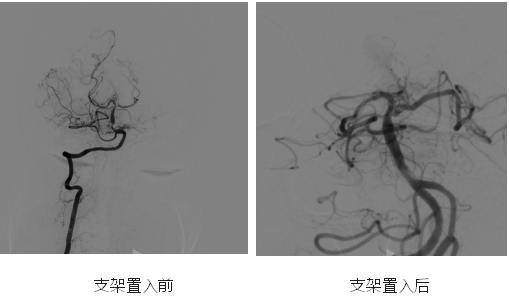

王婆婆此前因反复头晕在当地医院就诊,被确诊为“后循环缺血、基底动脉重度狭窄”。造影显示,其基底动脉下端狭窄达90%,还伴有左侧椎动脉起始部迂曲、左侧椎动脉V3和V4段开窗畸形等复杂血管问题。

经熟人推荐,王婆婆一家找到湖北省第三人民医院神经内科万跃教授团队。团队高度重视,立即反复细致分析评估其血管影像资料,充分论证手术可行性与风险应对方案,最终凭借丰富经验和扎实技术,决定为其行“基底动脉球囊扩张 + 支架置入术”。

“万教授愿意接纳我做手术,我就有了80%的信心,预感手术会成功。”手术前一天,王婆婆拉着管床医生严丹的手激动地说。手术中,王婆婆血管迂曲增加了操作难度,但万跃教授团队默契配合、技术娴熟、心态沉稳,精准完成球囊扩张与支架置入,成功开通基底动脉。